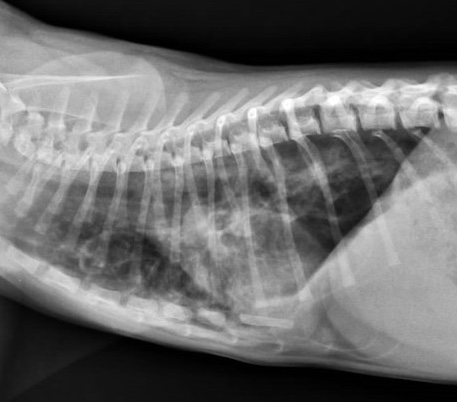

L’esame radiografico di norma si può eseguire senza sedazione; si può eventualmente eseguire una breve anestesia gassosa con induzione diretta. Viste le dimensioni della cavia, conviene eseguire di routine le proiezioni laterale e ventrodorsale di tutto il corpo, a meno che l’animale non sia gravemente debilitato e manovre stressanti poss...